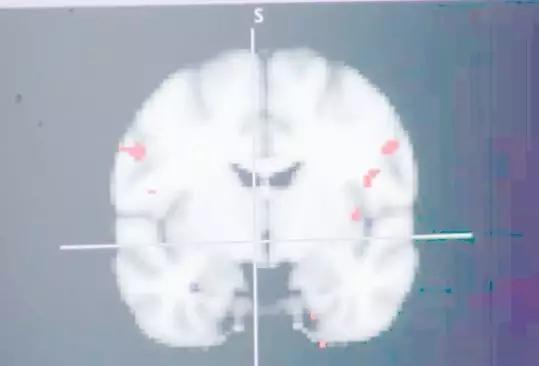

一名精神病学专家通过用核磁共振设备对多位肥胖症患者大脑进行扫描,把他们观看高脂食物时的脑区活跃程度与普通人对比后发现,他们对高脂食物极其敏感,在大脑眶额叶、脑腹和杏仁体等位置的反应较为活跃,说明大脑对高热量食物做出了强烈的反应。

他们在大脑中植入芯片,只是为了减肥

正常身材的人对高脂食物的反应

肥胖症患者对高脂食物的反应